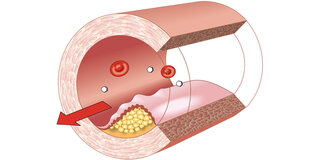

Arterienverkalkung

Arterienverkalkung

Arteriosklerose – gefährlicher Engpass

Gefäßverkalkung kann zu Herzinfarkt, Schlaganfall und anderen Durchblutungsstörungen führen. Mehr zu Ursachen, Therapie und Vorbeugung. zum Artikel